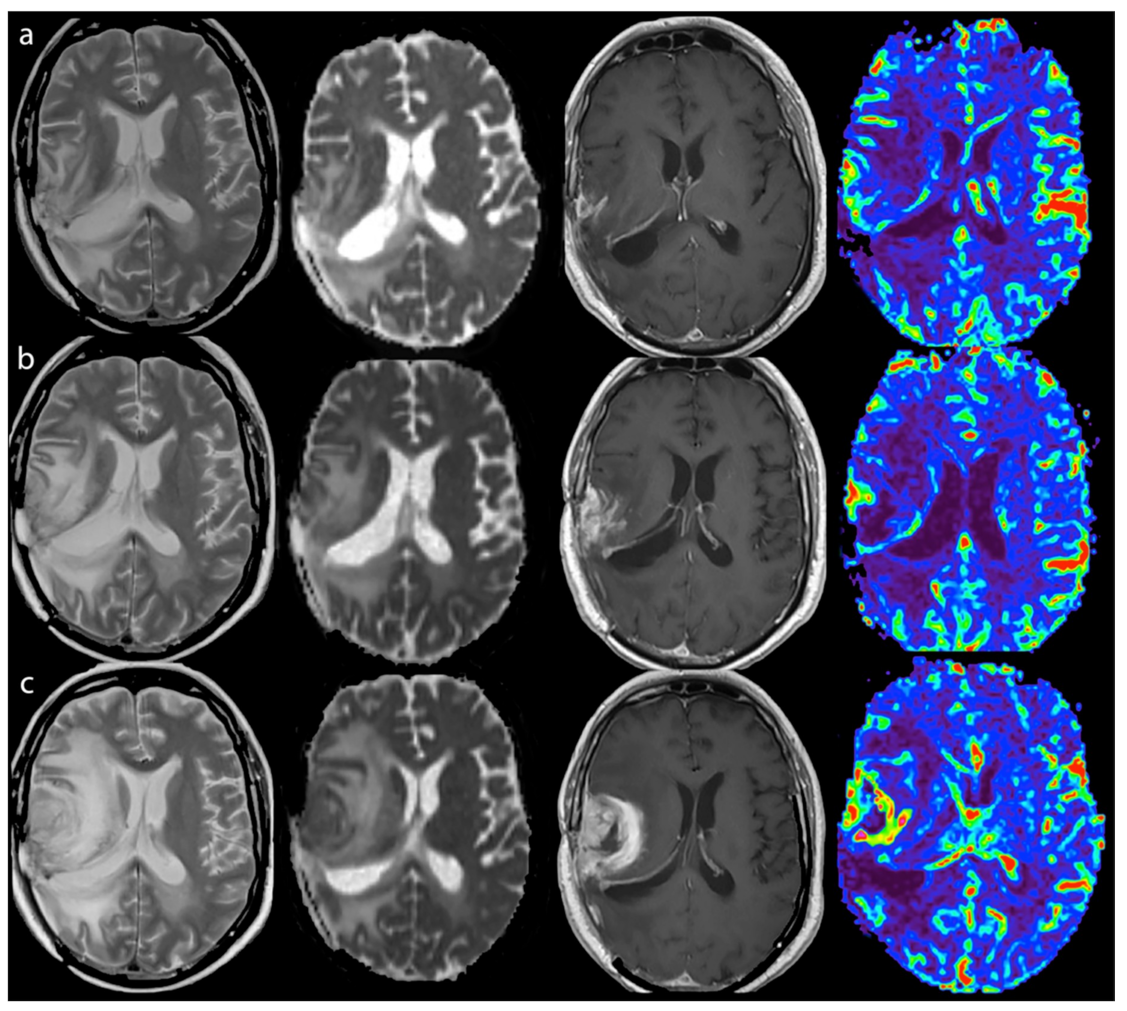

- Vrabec, M.; Van Cauter, S.; Himmelreich, U.; Van Gool, S.W.; Sunaert, S.; De Vleeschouwer, S.; Šuput, D.; Demaerel, P. MR perfusion and diffusion imaging in the follow-up of recurrent glioblastoma treated with dendritic cell immunotherapy: A pilot study. Neuroradiology 2011, 53, 721–731. [Google Scholar] [CrossRef]